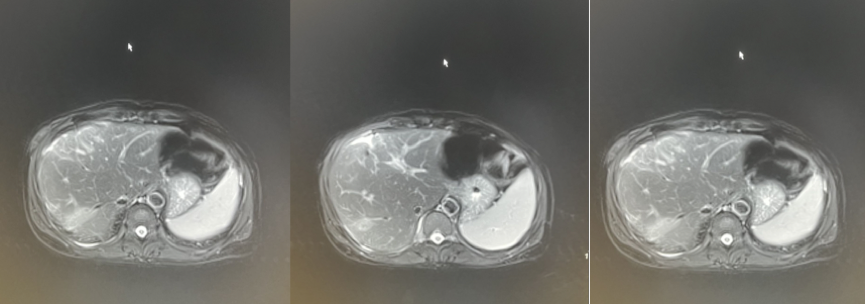

2020年7月1日术前CT检查示(图1),肝脏轮廓不整,边缘呈锯齿状改变,肝实质强化不均,肝S4段团块状异常强化,较大截面约51mm×55mm,肝细胞癌(HCC)?

图1.2020年7月1日术前CT